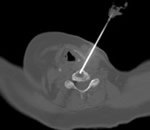

Biopsy of the cervical spine can be safely done with CT guidance. Image to the right is a case of hemangioma with an extra osseous component. The standard 13G bone biopsy needle is used.